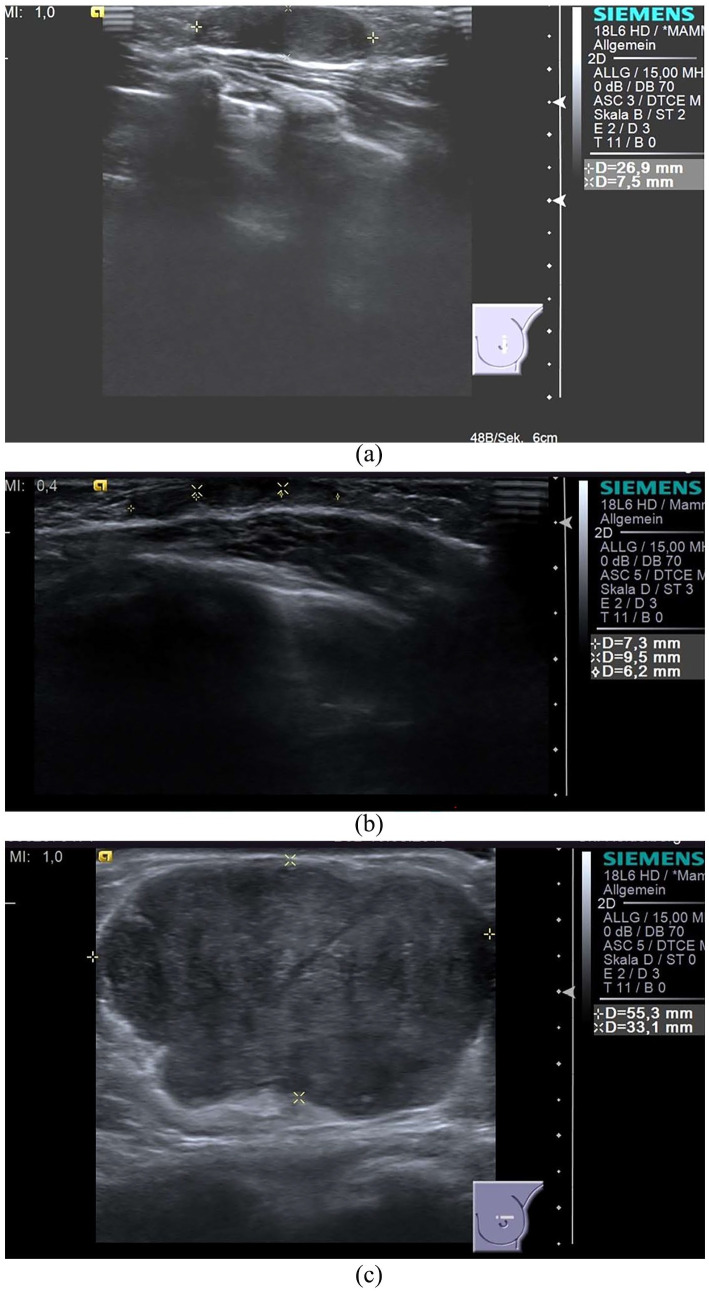

青少年纤维腺瘤通常见于青少年患者,具有独特的临床和组织病理学特征,这些特征与良性肿瘤的早期发病有关。青少年纤维腺瘤很少发生在青春期前,也可能在童年早期就被发现,这就提出了鉴别诊断和治疗的问题。我们提出一个病例非常早期的首次表现的青少年纤维腺瘤在一个2岁的病人。经过7年的临床观察和保守治疗,无进展。在9岁时,病变迅速生长,引起临床症状。手术完全切除,临床效果良好。组织学诊断为幼年纤维腺瘤。总之,青少年纤维腺瘤是青少年中最常见的乳腺肿瘤,可引起过度的单侧生长,导致大体不对称和疼痛。然而,它可以在儿童早期和经过几年的休眠期后被检测到,就像在这种情况下,导致青春期开始时突然大量生长。临床治疗应包括妇科、儿科和儿科外科的跨学科治疗方法,以平衡保守治疗的风险和益处。手术切除可以安全地推迟,直到必要时,由于临床症状。

Juvenile fibroadenoma typically is seen in the adolescent patient and has distinctive clinical and histopathological features that are related to the early onset of the benign tumor. Only rarely can juvenile fibroadenoma occur as a prepubertal lesion or may be detected earlier in childhood, raising questions about differential diagnosis and management of the lesion. We present a case of very early first manifestation of juvenile fibroadenoma in a 2-year-old patient. Under clinical observation and conservative management over a 7-year period, there was no progression. At the age of 9 years, rapid growth of the lesion occurred causing clinical symptoms. Complete surgical excision resulted in a good clinical outcome. Histologically, the diagnosis of juvenile fibroadenoma was made. In summary, juvenile fibroadenoma is the most common breast neoplasia in adolescents and may cause excessive unilateral growth resulting in gross asymmetry and pain. However, it can be detectable in early childhood and after a dormant period of several years, as in this case, lead to sudden massive growth at the onset of puberty. The clinical management should include an interdisciplinary treatment approach with gynecology, pediatrics, and pediatric surgery to balance the risks and benefits of conservative management. Surgical removal can be safely postponed until it becomes necessary due to clinical symptoms.